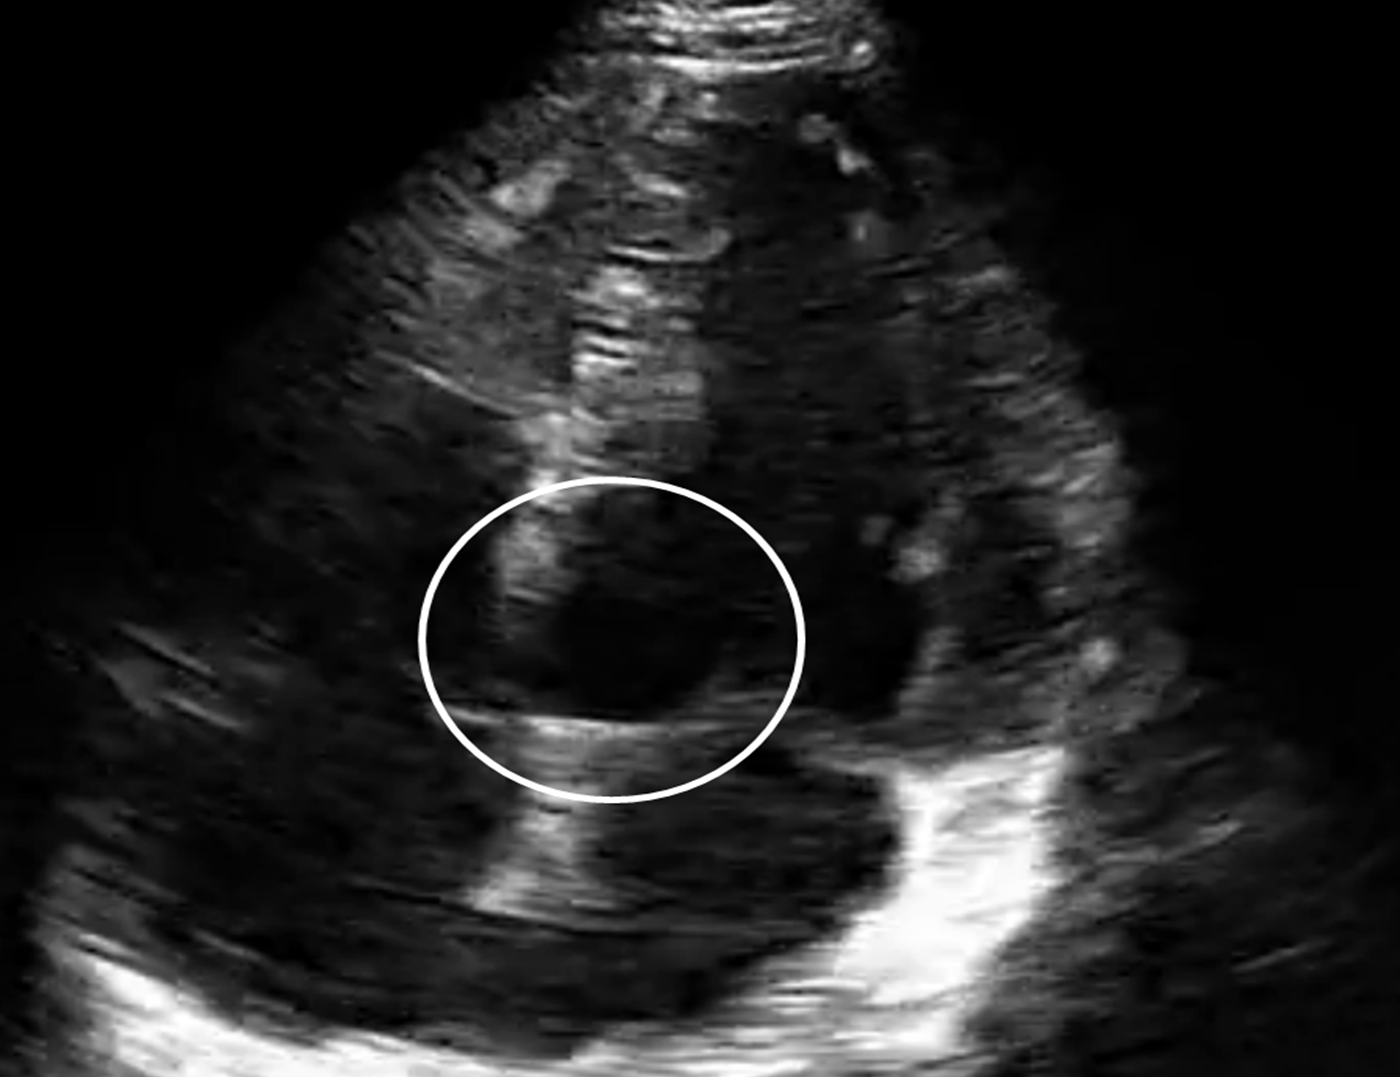

From www.researchgate.net

A bedside echocardiogram revealed massive pericardial effusion How To Do A Bedside Echo Bedside ultrasound should be used to answer specific questions in real time. Bedside echo is becoming an integral part of intensive care medicine, offering real time haemodynamic evaluation. Be surgical with the probe. How to do a level 1+ echo. Focussed echo in life support (fels) is used to define cardiac pathologies such as cardiogenic shock, pericardial tamponade,. Ultrasonography is. How To Do A Bedside Echo.